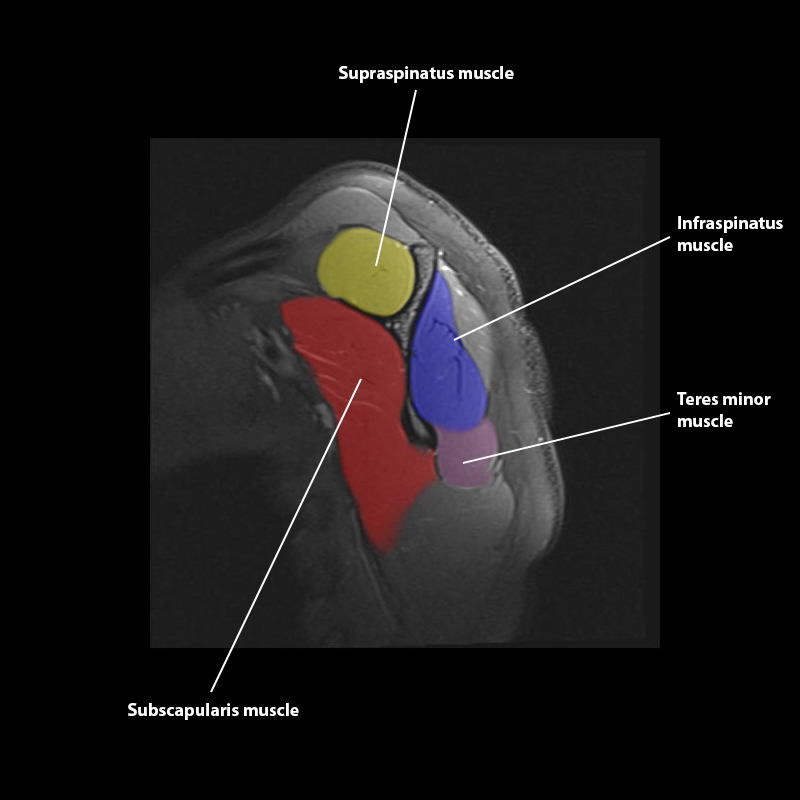

Shoulder MRI Anatomy